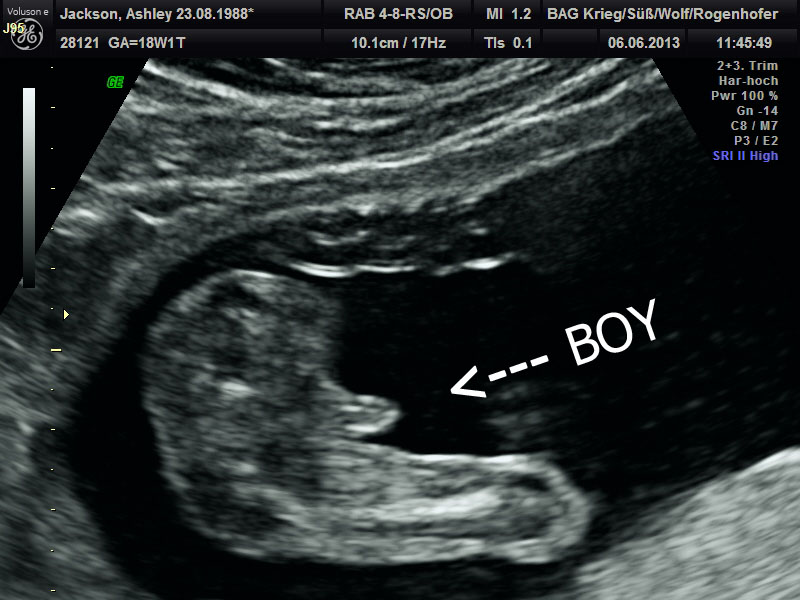

| Definitely a boy! |